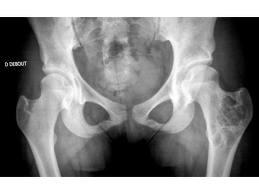

La scannopelvimétrie, c'est quoi?

Il s'agit d'un moyen radiologique utiliser en Obstétrique, permettant d'explorer le bassin osseux chez la femme dans le but d'analyser ses structures, et réaliser certains mesures qui sont nécessaires à l'obstétricien pour décider l'acceptabilité ou non, de l'accouchement par voie naturelle chez certaines femmes enceintes présentant des situations obstétricales particulières : utérus cicatriciel, présentation du siège, macrosomie (poids du bébé estimé supérieur à 4KG500), déformations acquises ou congénitales du bassin osseux...